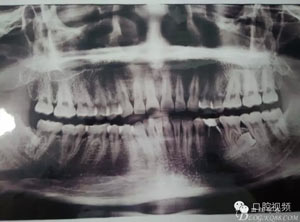

圖1.術(shù)前的全景片影像檢查,35移位至36、37之間。